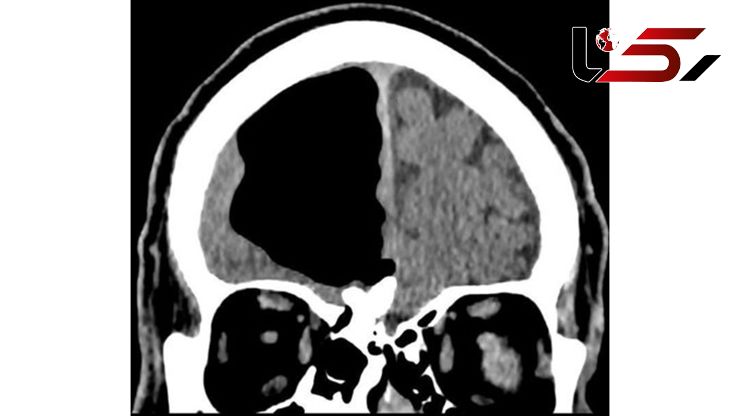

پزشکان با اسکن مغزِ یک مرد ایرلندی به حفره‌ای به اندازه یک سیب در جمجمه او و فضایی که در واقع مغز او باید قرار داشته باشد، برخورد کردند.

اگر چه نتیجه آزمایش خون این فرد طبیعی بود ولی تصویربرداری‌ها از مغز او وجود یک حفره عجیب ۹ سانتی متری از هوا را در جمجمه نشان می‌داد.به غیر از مشکل ضعف که تا سه روز ادامه داشت، کادر پزشکی ازسلامت کامل این فرد بدون هیچ گونه پریشانی، ضعف ظاهری یا مشکلات بینایی و تکلمی خبر دادند.

این حفره به عنوان یک پنوماتوسل، حفره‌ای پرفشار از هوا، در سمت راست لوب پیشانی این فرد قرار گرفته است. این دسته از حفره‌ها معمولا در بیمارانی که سابقه جراحی مغز یا ابتلا به انواع مختلف عفونت را داشته‌اند معمول است ولی اندازه آنها بسیار کوچکتر است.

اسکن مغزی همچنین یک تومور خوش خیم استخوانی و یک سکته ناقص در مغز او را نشان داد. به منظور درمان این حفره، پزشکان پیشنهاد جراحی به او را دادند که با توجه به خطرات ناشی از جراحی، این مرد ایرلندی پیشنهاد را نپذیرفت ولی در عوض قرار شد انواع مختلفی از داروها را برای کمک به پیشگیری از سکته‌های آینده دریافت کند.